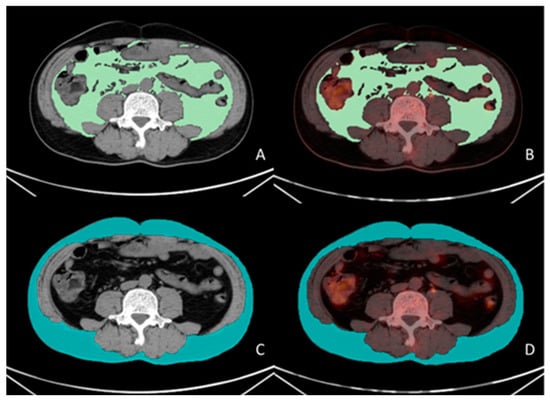

All PET/CT images were delineated by two nuclear medicine physicians, who were blinded to the clinical data. The VAT SUVmean, SAT SUVmean, and skeletal muscle cross-sectional area were obtained using the LIFEx software version 7.4.0. VAT and SAT regions at the L4–L5 vertebral level across three consecutive CT slices were delineated based on CT attenuation values, ranging from −50 Hounsfield units (HU) to −150 HU [13]. These CT-defined VAT and SAT regions were mapped onto the corresponding PET/CT fusion images to acquire the VAT SUVmean and SAT SUVmean, as shown in Figure 1. The total skeletal muscle cross-sectional area at the L3 level (including the psoas major, erector spinae, quadratus lumborum, transversus abdominis, internal oblique, external oblique, and rectus abdominis muscles) was delineated based on the CT attenuation range (−29 HU to 150 HU) on CT images, as shown in Figure 2. The skeletal muscle index (SMI) at L3 was calculated as follows: skeletal muscle cross-sectional area at L3 (cm2)/height squared (m2) [22].

Figure 1. Measurement methodology for VAT and SAT SUVmean. A 56-year-old male patient with gastric cancer underwent preoperative 18F-FDG PET/CT examination. Visualized using LIFEx software (version 7.4.0). VAT (green color in (A)) and SAT (blue color in (C)) regions were delineated on three consecutive CT slices at the L4–L5 vertebral level based on the CT attenuation range (−50 to −150 Hounsfield units [HU]). The CT-defined VAT and SAT regions were subsequently co-registered with corresponding PET/CT fusion images (green color in (B), blue color in (D)), yielding a VAT SUVmean of 0.43 and an SAT SUVmean of 0.32.